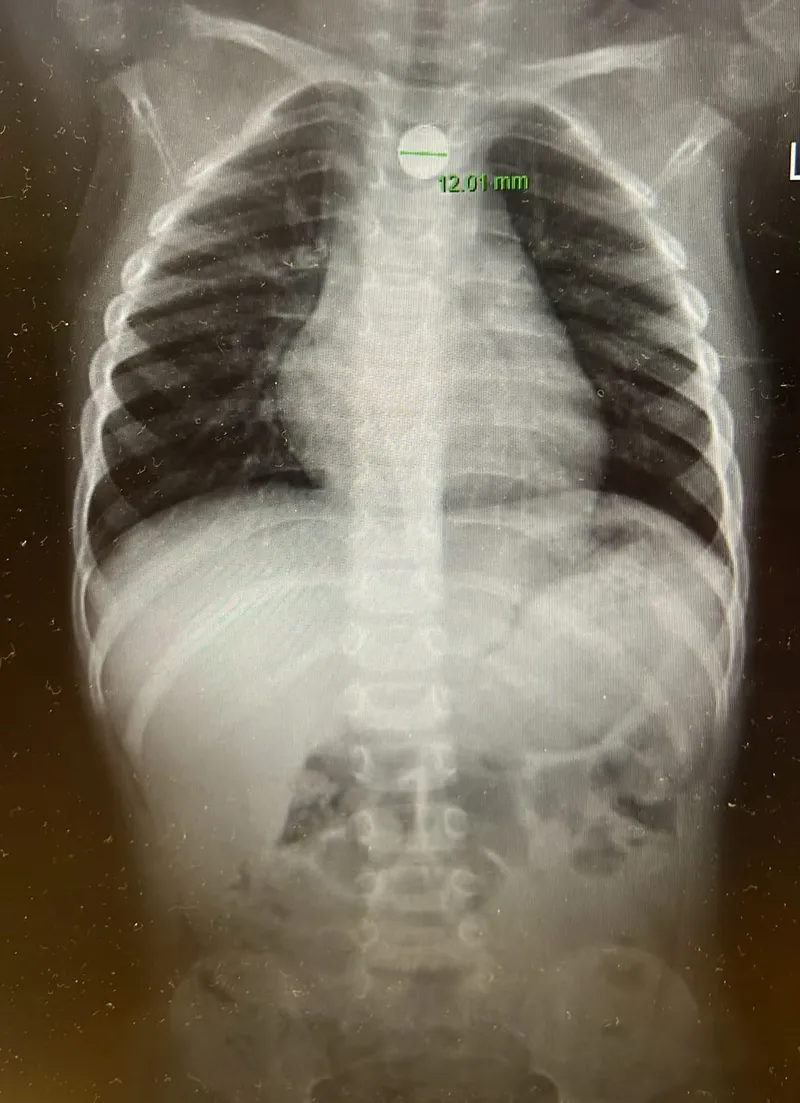

עם הגעתם למלר"ד ילדים, קיבל את פניהם ד"ר אהוד רוזנבלום. צילום חזה מהיר אישר כי הסוללה תקועה בוושט – מצב חירום רפואי מובהק. הילד הוכנס במהירות לחדר ניתוח תחת ידיו של ד"ר אייל זיפמן, מנהל שירות גסטרואנטרולוגיה ילדים. "הסוללה נמצאה נעוצה בוושט ונשלפה בשלמותה באמצעות גסטרוסקופיה", הסביר ד"ר זיפמן.